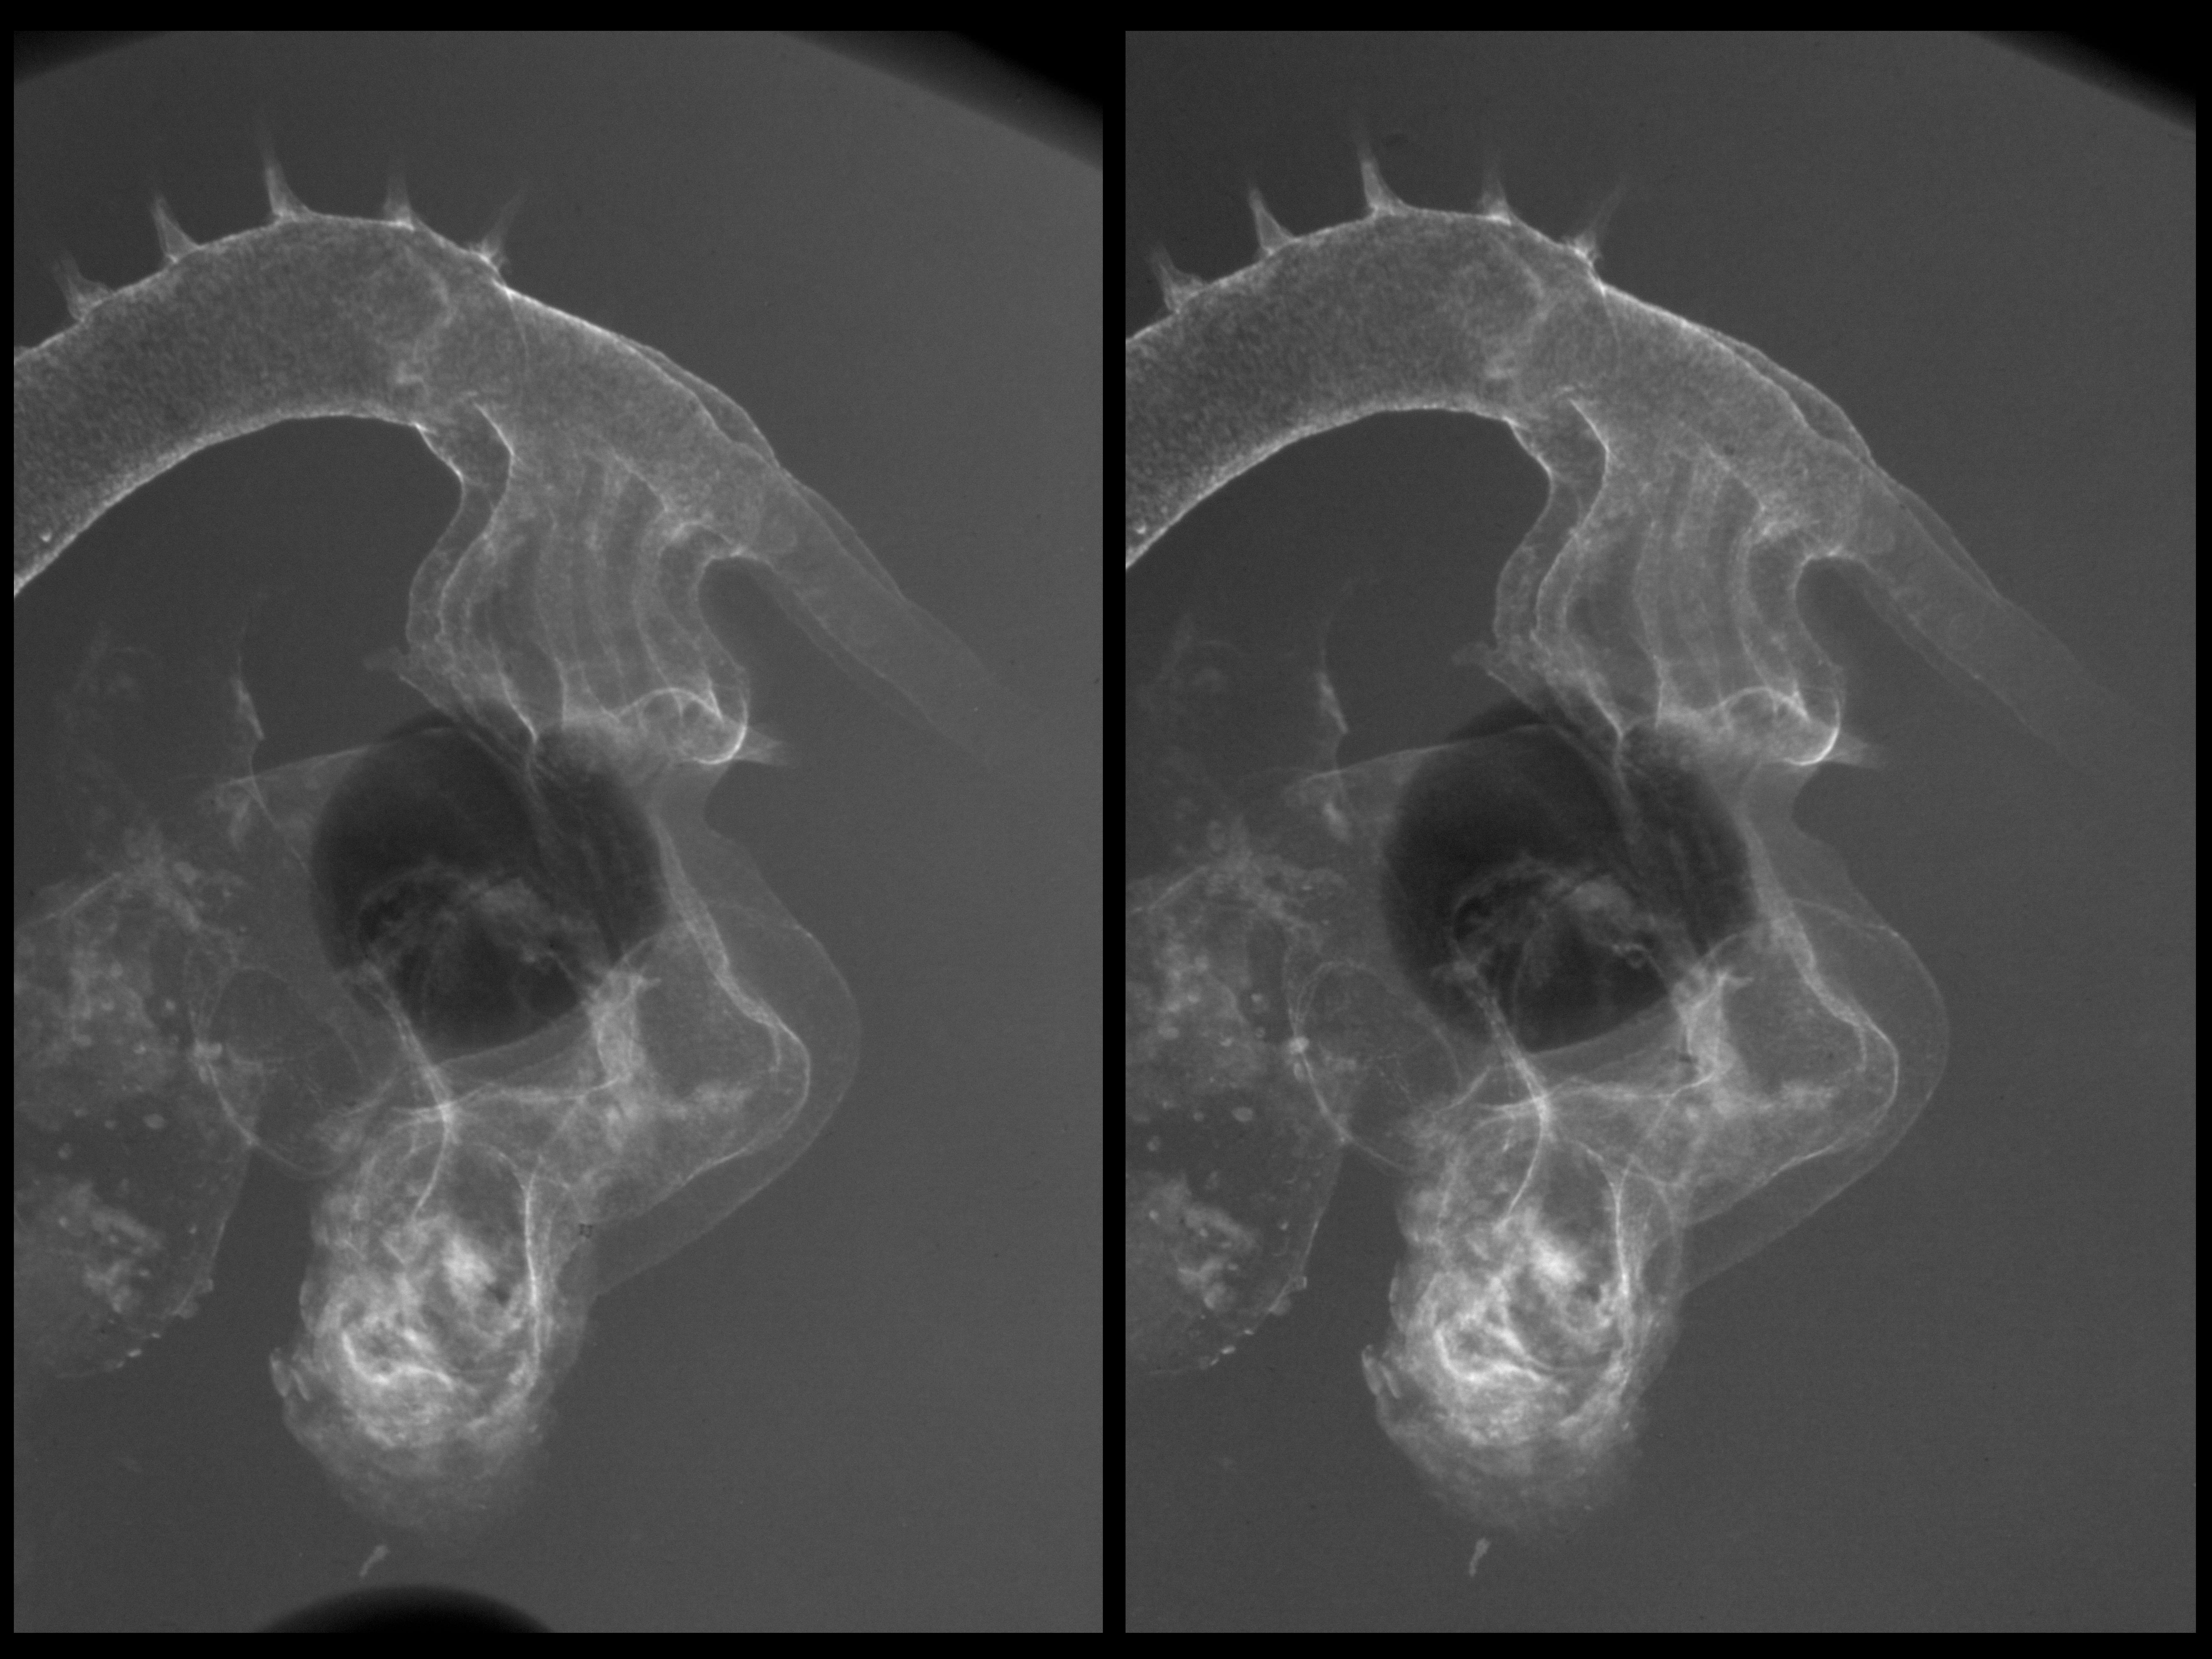

Chick Embryo Microangiography

Hamburger-Hamilton (HH) Stage 21 (approx. 3.5 days)

Stereo X-Ray Micrographs